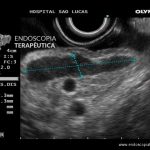

GIST gástrico